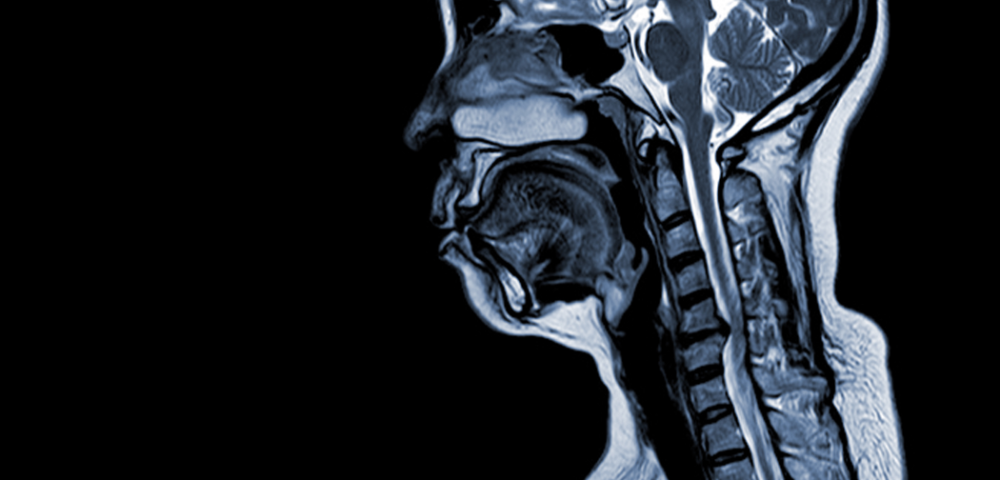

Ce ar trebui să cunoști despre mielopatie, care este legătura între aceasta și hernia de disc